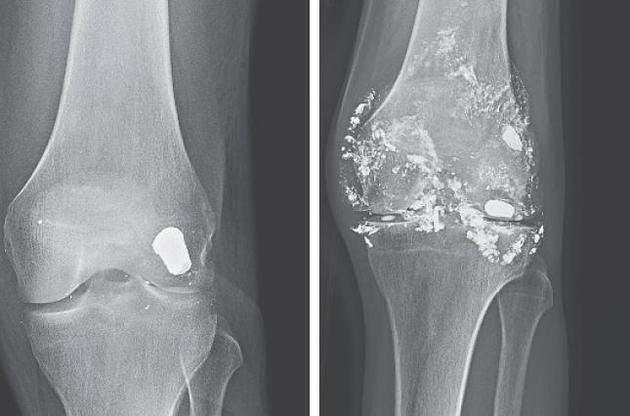

46-річний пацієнт звернувся до однієї з лікарень з Чикаго зі скаргами на посилення хронічного болю в лівому коліні. 14 років тому він отримав поранення в ногу, рентгенографія показала, що куля застрягла в кістці, тому медики вирішили її не витягувати.

Після того, як чоловік знову звернувся за допомогою, йому ще раз зробили рентгенографію і виявилося, що за 14 років куля розпалася на частини, які залишилися в тканинах колінного суглоба. В результаті у пацієнта в суглобі скупчилася велика кількість рідини. До того ж у нього було виявлено підвищений вміст свинцю в крові та анемія, яка часто супроводжує отруєння свинцем. Щоб вивести його з організму, пацієнту призначили хелатну терапію. Вона застосовується для лікування отруєння важкими металами, такими як свинець або ртуть.